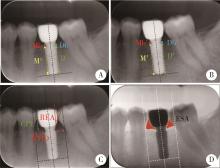

图1

影像学测量方法"